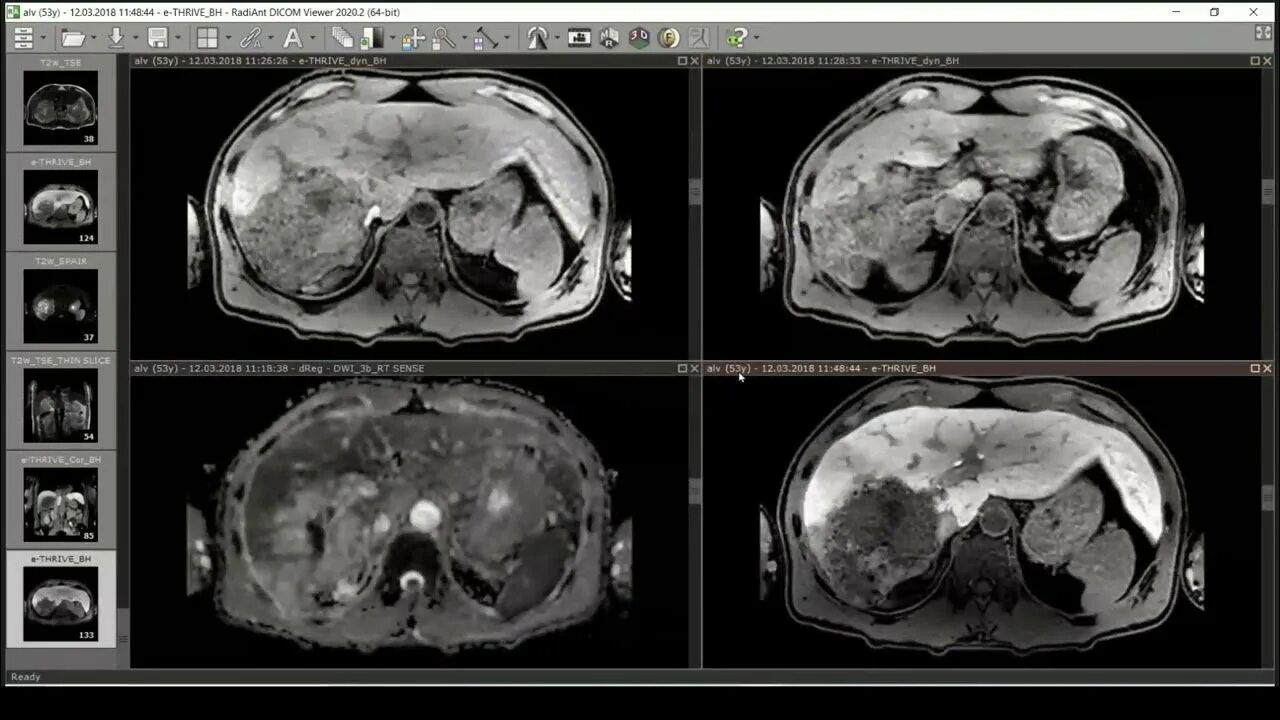

Дифференциальное мрт